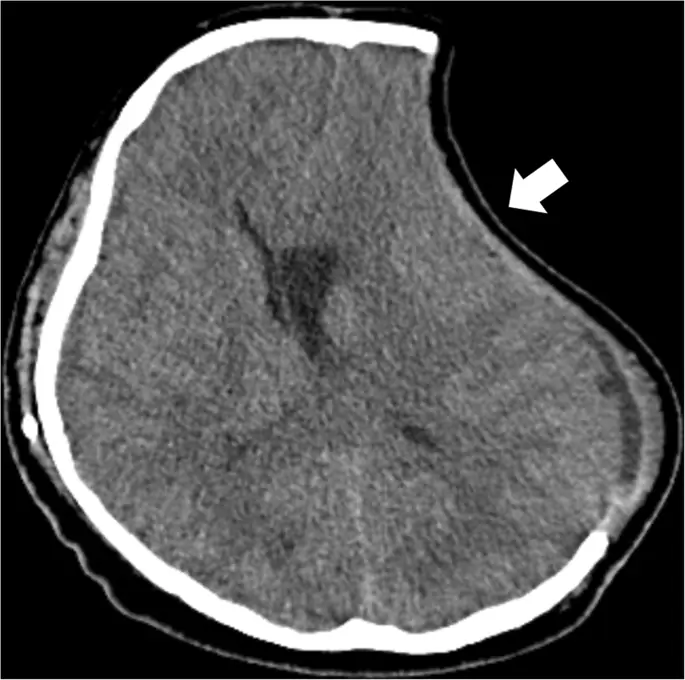

Нарушения спинномозговой жидкости (CSF) часто встречаются после ДК для инфаркта головного мозга: от 20 до 80% развиваются гигромы и от 30 до 40% внутренней сообщающейся гидроцефалии (рис. 8) (52, 53, 54). По крайней мере одна треть этих нарушений CSF, кажется, разрешается или спонтанно или после краниопластики. У остальных пациентов может потребоваться вентрикуло- и / или субдуро-перитонеальный шунт, чтобы избежать дальнейшего неврологического ухудшения.

figure8

Гигрома, возникающая после ДК. Осевая КТ показывает ипсилатеральную и контралатеральную субдуральную гигрому (черные стрелки), которая произошла после левосторонней гемикраниэктомии. Кроме того, наблюдается большой сбор эпидуральной жидкости (белая стрелка)

Изображение в полном размере